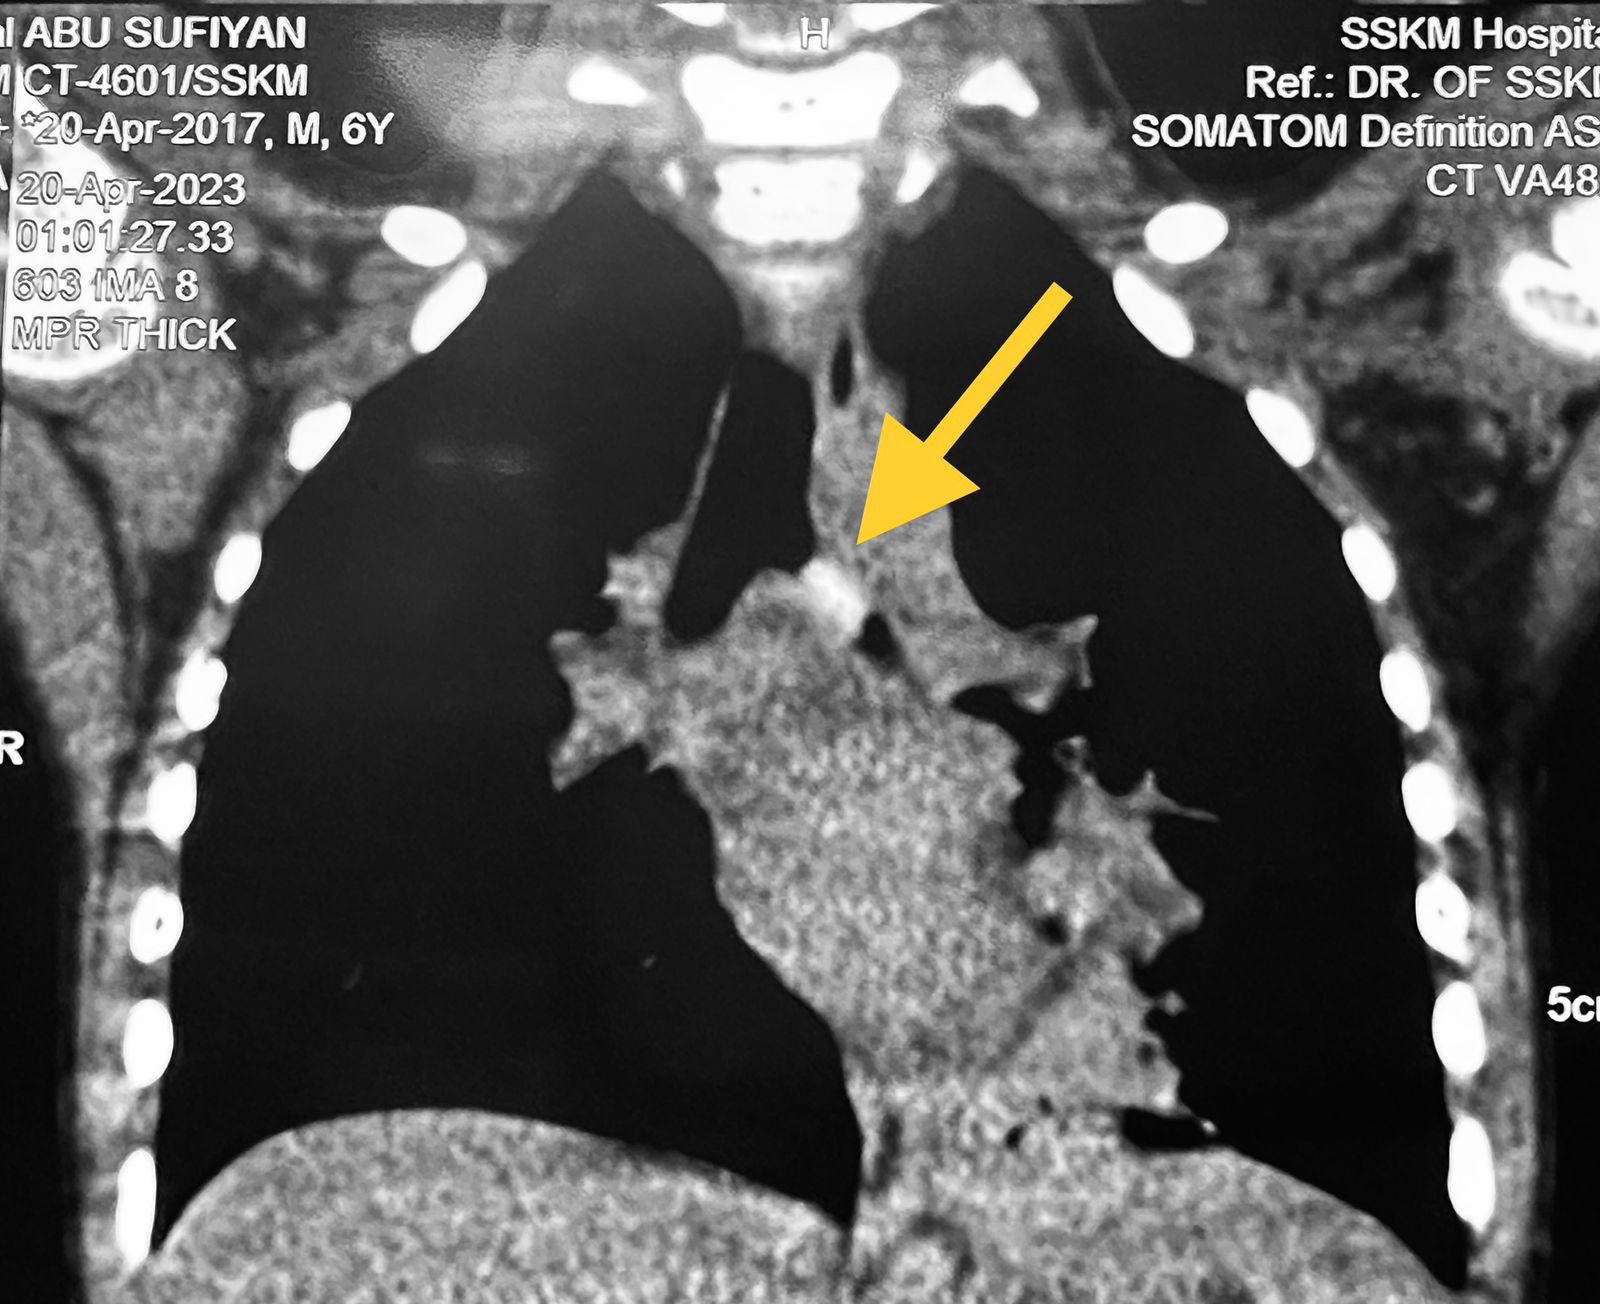

প্রতিবেদন : মৃত্যুর মুখ থেকে এক শিশুকে ফিরিয়ে আনল কলকাতা (Kolkata) এসএসকেএম (SSKM)। নাম আবু সুফিয়ান। বয়স মাত্র ছ’বছর। বাড়ি মুর্শিদাবাদের (Murshidabad) লালগোলার প্রত্যন্ত এলাকায় নতুন গ্রাম। ইংরেজি মাধ্যম স্কুলের প্রথম শ্রেণির ছাত্র। এবার জমিতে ভুট্টার ভাল ফলন হয়েছিল। বাবা গোলাম কিবরিয়া খেতের ভুট্টা ছাদে রোদে শুকাতে দিয়েছিল। ওই ভুট্টা নিয়ে খেলা করছিল আবু। আচমকা আড়াই সেন্টিমিটারের মতো ভুট্টাদানা শ্বাসনালি দিয়ে ফুসফুসে আটকে যায়। দমবন্ধ হওয়ার পরিস্থিতি তৈরি হয়। স্থানীয় নার্সিংহোম থেকে মুর্শিদাবাদ মেডিক্যাল কলেজে নিয়ে যাওয়া হলেও ফুসফুসে আটকে থাকা ভুট্টার দানা বের করা যায়নি। কিন্তু পরিস্থিতি খারাপ হতে থাকে। শ্বাসকষ্ট। সেই সঙ্গে রক্তবমি। এরপরেই বুধবার বিকেলে ভর্তি করানো হয় এসএসকেএমে। বৃহস্পতিবার সকালে জরুরি ভিত্তিতে অপারেশন হয়। ব্রঙ্কোস্কপির মাধ্যমে ফুসফুসে আটকে থাকা ওই ভুট্টার দানা বের করা আনা হয়। জটিল এই অস্ত্রোপচারটি চলে ইএনটির বিভাগীয় প্রধান ডাঃ অরুণাভ সেনগুপ্তের তত্ত্বাবধানে। অত্যন্ত সন্তর্পণে বের করে আনা হয় ভুট্টার দানা। আপাতত শিশুটি সুস্থ। শিশুর বাবা পেশায় কেবল অপারেটর। গুলাম কিবরিয়া বলেন, পিজির (SSKM) ডাক্তারা আমার ছেলের জীবন ফিরিয়ে দিলেন। ভাবিনি ও মৃত্যুর মুখ থেকে শেষ পর্যন্ত ফিরে আসবে।